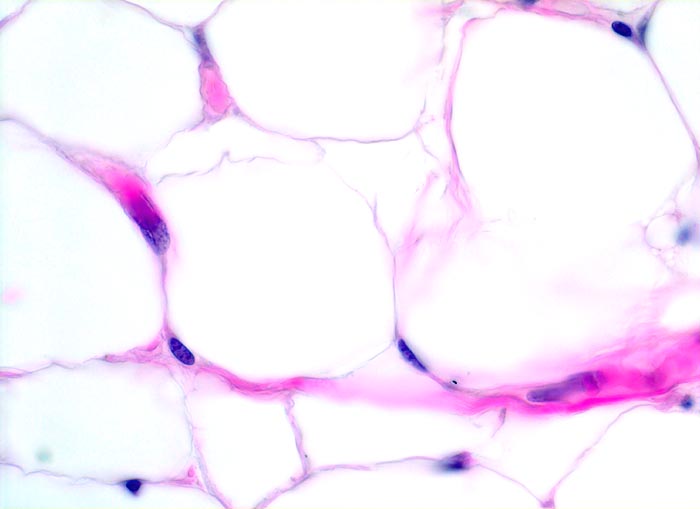

PathoPic – image database / PathoPic ID 4061 - reifes Fettgewebe

reifes Fettgewebe

Reife Fettzellen mit reichlich transparentem Zytoplasma. Das Fett wurde durch die Fixation herausgelöst. Am Rand der Zellen ein schmaler flachgedrückter Kern mit feinem Chromatin.

400